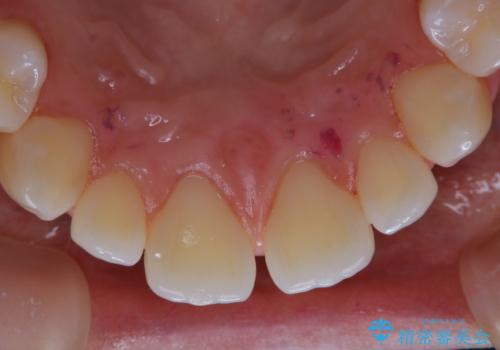

一見きれいに見える歯でも、染め出し(歯垢染色液)を使うとこのように歯と歯茎の境目や、歯と歯の間などに磨き残しがあることがわかります。歯磨きには、いつも気をつけているから磨き残しはナシと思っていても、実際完璧に磨ききることはなかなか難しいです。歯科医院にて、専門の機械で定期的なPMTCを行うことが大切です。